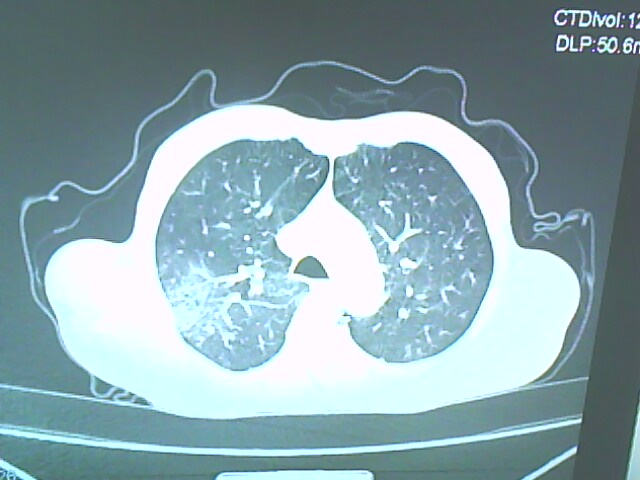

患者,男,66岁,以咳嗽、咳痰伴胸痛来就诊。

胸片提示右上肺占位病变。请各位老师看看ct。

考虑癌性空洞可能性大,空洞内壁不规则,病灶周围模糊,分叶、有毛刺

空洞内壁不规则,病灶周围模糊,分叶、毛刺呈日光放射状,突然截断,支持考虑癌性空洞

考虑右肺上叶后段周围型肺癌并癌性空洞形成。

考虑癌性空洞可能性大,内壁不规则,洞壁薄厚不均呈结节状突起,边缘模糊,分叶,毛刺

右上肺后段肺癌:

典型癌性空洞(偏心性,壁厚薄不均,内壁不光整),周围毛刺较僵硬,且有刺突征和血管聚集征